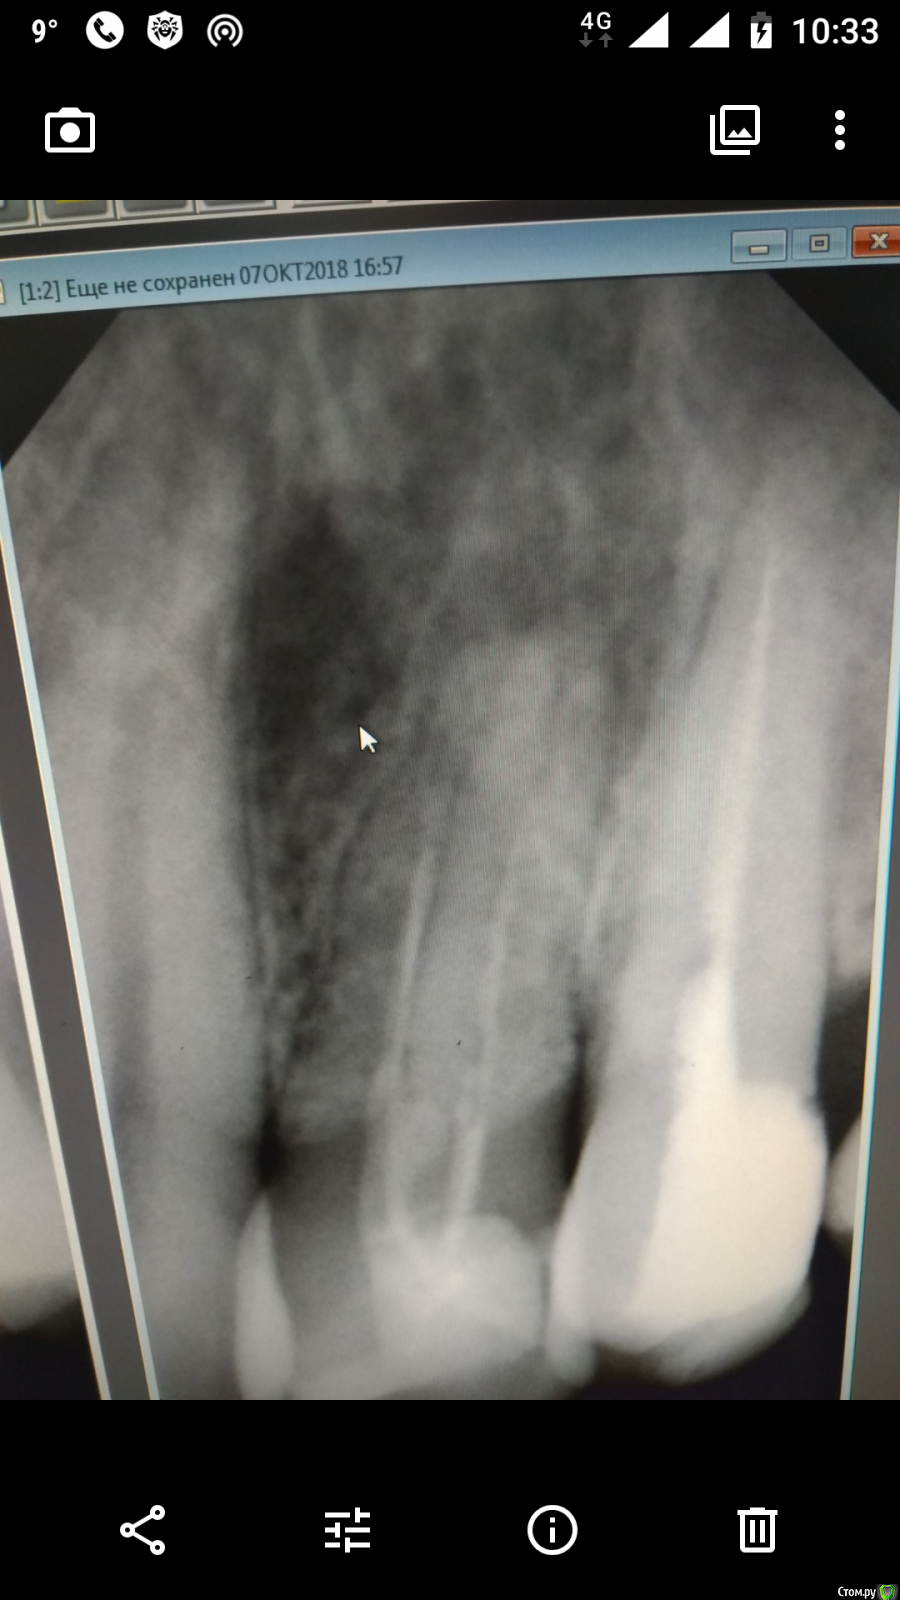

SeregafromMoscow Опубликовано 16 октября, 2018 Поделиться Опубликовано 16 октября, 2018 (изменено) Добрый день, Нужен совет специалиста по прикреплённом фото.Ныла верхняя челюсть без сильных болей но мешала. После фото врач решил перепломбировать данный зуб. Появилось пару вопросов:1. Есть ли в этом смысл?2. Могла ли после повторной прочистки каналов пойти кровь немного из этой же ноздри (где то через час) или это совпадение? Давить и ныть стало меньше почти перестало.Три дня по рекомендации врача хожу с открытым зубом каналами ваткой. Заранее спасибо Изменено 16 октября, 2018 пользователем SeregafromMoscow Ссылка на комментарий

red_butler Опубликовано 16 октября, 2018 Поделиться Опубликовано 16 октября, 2018 1. Есть ли в этом смысл? есть Три дня по рекомендации врача хожу с открытым зубом каналами ваткой. врача стоит поменять Ссылка на комментарий